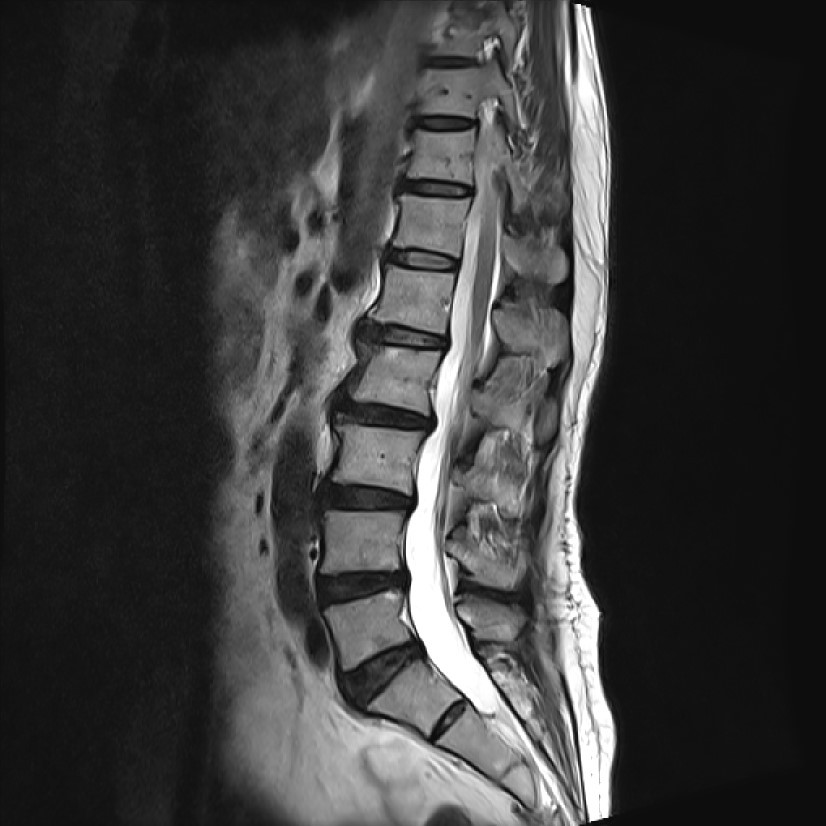

화면 캡처 2024-09-21 144447.jpg

허리뼈 2,3,4,5번 모두 약간의 돌출 (protrusion), 팽윤 (Bulging)이 있어 보였습니다. 그리고 다른 사진들과 같이 판단했을 때 허리뼈 3번/4번의 오른쪽 foraminal HNP(디스크 탈출증), 허리뼈 5번/엉치뼈 1번 왼쪽 foraminal stenosis(협착)이 관찰되었습니다.

이 정도 디스크 탈출증은 그렇게 심한 편도 아니고 적절한 주사요법을 시행했는데 보행에 영향을 줄 정도의 방사통이 발생한다는 것은 납득이 가지 않았습니다. 그리고 보통의 디스크 탈출증이 허리에 있는 환자들은 코어 근육 사용법을 잘 모릅니다. 코어 근육을 사용하는 방법을 교육하고 유지할 수 있게 되면 코어 수축 중 통증이 줄어드는 느낌을 받게 됩니다. 물론 방사통도 많이 감소됩니다. 그런데 장모님은 코어 수축을 잘하시고 코어 수축 중에도 다리 뒤쪽의 방사통과 이상감각에 변화가 없었습니다. 허리 마사지로 충분히 이완시켜 드리고 코어 자극을 시행했습니다. 운동을 하시면서 통증이 줄어들었다고 립서비스를 해주시더군요. 누워서 시행한 여러 가지 치료에 대해 반응이 있었다고 생각했지만, 립서비스라고 생각한 이유는 걸을 때 비대칭 보행이 여전히 남아 있었기 때문입니다.